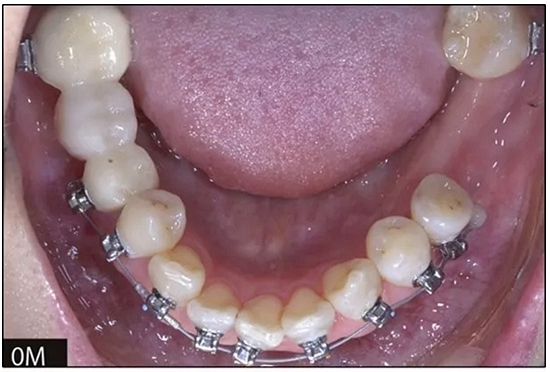

完全固定的Damon Q設(shè)備(加利福尼亞州Glendora的Ormco)與制造商指定的弓絲和附件一起使用。下頜弓,一開始放入0.014英寸的鎳鈦弓絲,5個(gè)月后放入0.014×0.025英寸的鎳鈦弓絲。舌側(cè)扣和鏈圈放置在下頜尖牙和第二前磨牙上以控制扭轉(zhuǎn)。在治療的第7個(gè)月,將下頜弓絲換成0.017× 0.025英寸的β鈦絲。另一個(gè)舌側(cè)扣和鏈圈放置在下頜左側(cè)第三磨牙上以提供近中牽引力(圖9)。在16個(gè)月的治療結(jié)束時(shí),所有的扭轉(zhuǎn)都得到了矯正,缺牙間隙縮小到8 mm(圖8),但由于頰側(cè)骨板的嚴(yán)重吸收,牙槽嵴的寬度仍然很窄(約3 mm)(圖9)。通過正畸移動(dòng)下頜左側(cè)第二前磨牙,在前磨牙之間產(chǎn)生一個(gè)種植部位。在第一和第二前磨牙之間的弓絲上放置一個(gè)推簧,并將舌側(cè)扣和鏈圈放置在第一前磨牙和第三磨牙之間(圖9),在頰側(cè)和舌側(cè)施加力。施力均為輕力,每個(gè)表面上約2盎司(28.3 cN)以控制牙根側(cè)面的吸收。

圖8

圖9